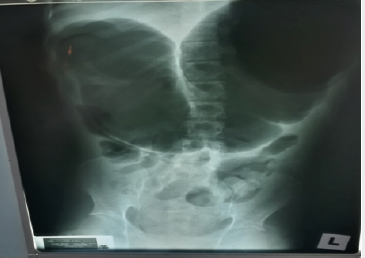

Patients with volvulus are commonly elderly, debilitated, and bedridden. Often, the patient has a history of dementia or neuropsychiatric impairment. As a result, only a limited history is available (Figure 2). More than 60-70% of patients present with acute symptoms; the remainder present with subacute or chronic symptoms. A history of chronic constipation is common. The patient may describe previous episodes of abdominal pain, distention, and obstipation, which suggest repeated subclinical episodes of volvulus [7]. The disease predominantly affects the females. If persistent, volvulus will cause vascular compromise which may proceed to caecal gangrene and bowel injury and carries a high mortality, up to 40%. [1]. Conventional radiography demonstrates a disproportionate distention of the right colon against a collapsed left colon, small bowel dilatation and proximal obstruction signs may occur depending on the time of onset [8-10].

The focal rounded air-filled cecum may present as a loop with haustral markings resembling a coffee bean; which appears as a dilated bowel loop with an inverted “U” shape converging at the site of torsion, and a thickened central radiopaque line composed by the walls of the two part of the colon that are adjacent to each other. Doppler USG may lead to make a definite diagnosis by showing twisted mesenteric vessels [11], and CT may be more diagnostic by demonstrating cecal distension, cecal apex in left upper quadrant, mesenteric whirl, ileocecal twist, and small bowel distension [12]. An important sign to look for is the “whirl sign” that consists of a whirlpool pattern of swirling structures including collapsed bowel loops, mesenteric fat and engorged ileocecal vessels (Figure 3). This finding, associated to a dislocated enlarged cecum, is acknowledged to be diagnostic of volvulus [9,13]. The treatment of caecal volvulus preferred surgical procedure for the treatment of patients with cecal volvulus is right hemicolectomy [7].

In our opinion this patient seems to be suffering from double pathology: Chronic large bowel obstruction due to post-op adhesion, and Cecal Volvulus due to congenital predisposing factors. Radiology plays a role to diagnose caecal volvulus since there is no specific symptoms and signs of caecal volvulus except those of intestinal obstruction. There were classic plain X-ray abdomen of coffee bean sign of caecal volvulus [8-10] and CT abdominal features of caecal volvulus [12,13] in this patient. Mildly low sodium level and high urea changes indicate dehydration due to bowel obstruction. An elevated white blood cell (WBC) count may indicate bowel ischemia, peritoneal infection with or without gut perforation, or systemic sepsis. However, there was no features of sepsis clinically in this patient preoperatively. Therefore, bowel ischemia is the most likely cause of leukocytosis in this case preoperatively. Different treatment and results are reported by Consorti ET and Liu TH [1]: Barium enema sporadic reports of reduction after barium enema. The success rate is unknown. This modality is not usually recommended as a therapeutic option.